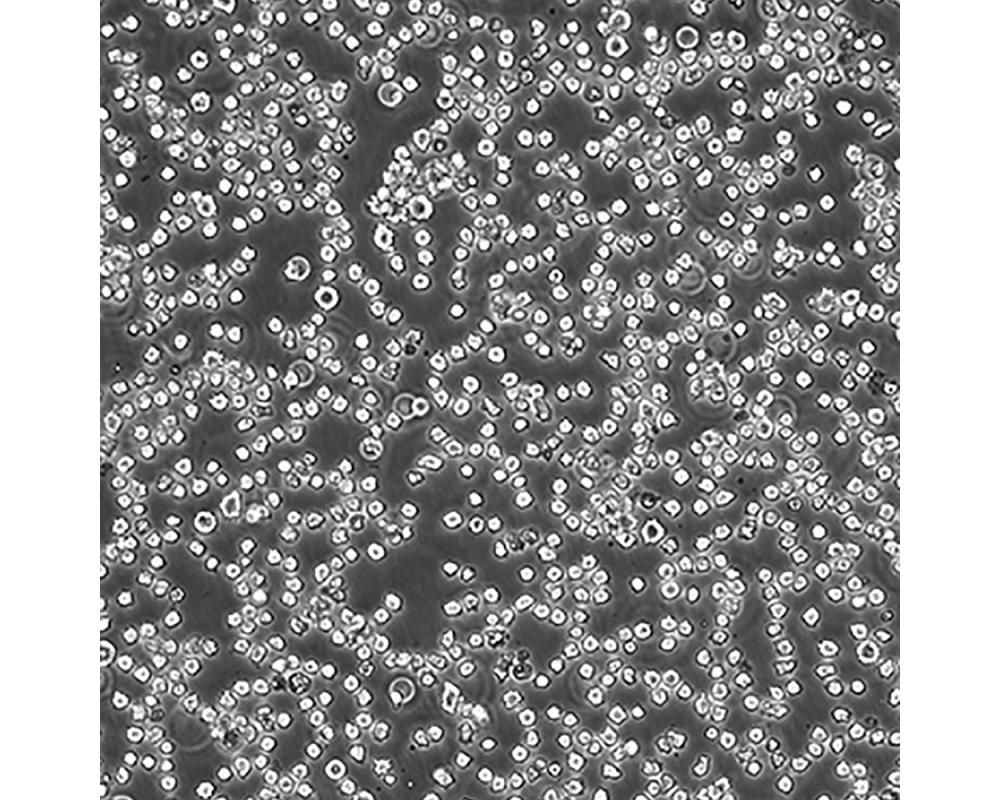

產品名稱 DB

中文名稱 人彌漫性大B細胞淋巴瘤細胞

組織來源 彌漫性大B細胞淋巴瘤;男性

生長特性 懸浮

培養基 DMEM90%;FBS10%;1%雙抗。

傳代方法 Maintain cultures at a cell concentraion between between 1 X 10(5) and 1 X 10(6) viable cells/ml.

培養條件 Atmosphere: Air, 95%; CO2, 5%。Temperature: 37℃